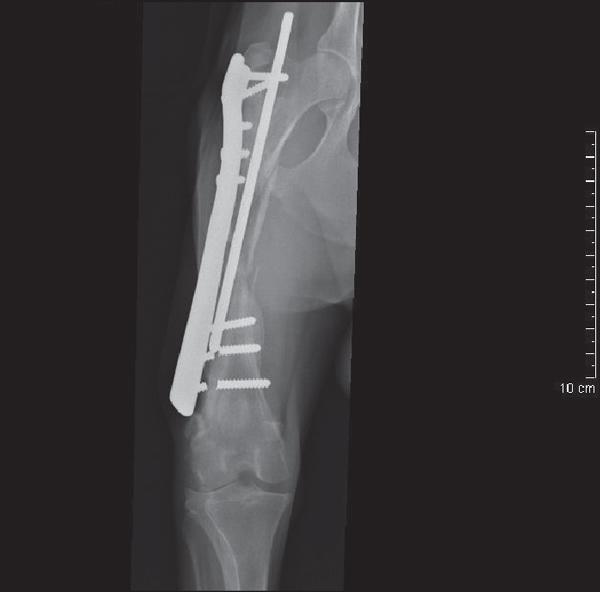

A three-year-old male working border collie with an infected femoral nonunion fracture was managed in a two-stage procedure involving debridement and omentalisation, followed by stabilisation with a bone plate and an autogenous cancellous bone graft. Osseous union was documented radiographically 16 weeks after surgery. Telephone follow-up one year later revealed the dog had returned to full working function without evidence of lameness. To the authors' knowledge, this is the first clinical case described in the veterinary literature using omentalisation as an adjunct to the management of an infected, biologically inactive nonunion fracture.

一只三岁雄性工作边境牧羊犬,患有感染性股骨骨不连骨折,采用两阶段手术治疗,包括清创和网膜化,随后使用骨板和自体松质骨移植物进行稳定。术后 16 周影像学显示骨愈合。一年后的电话随访显示,该犬已完全恢复正常工作功能,无跛行迹象。据作者所知,这是兽医文献中首次描述使用网膜化作为感染性、生物活性骨不连骨折治疗的辅助手段的临床病例。